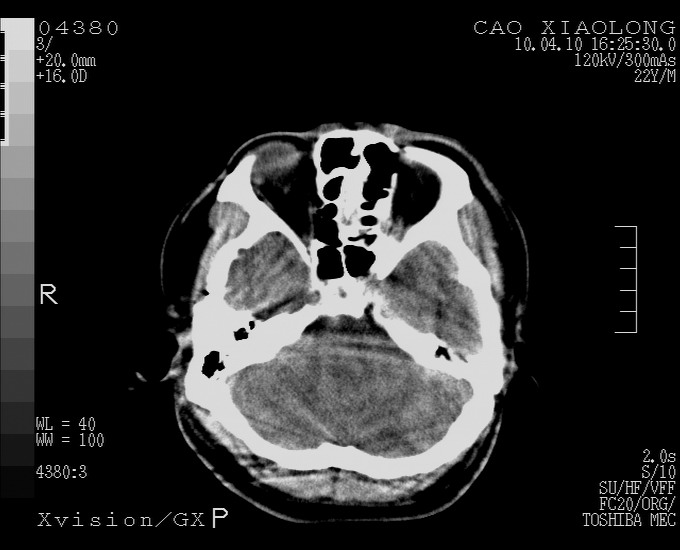

以下是引用随光逐影在2010-4-11 11:00:00的发言:[br]1)左侧额颞顶部硬膜下血肿。2)蛛网膜下腔出血。3)右侧颞顶部颅骨线形骨折。[br][br]20小时后复查:左侧额颞叶脑挫裂伤;左侧额颞顶部硬膜下血肿及蛛网膜下腔出血有吸收表现;右侧颞顶部颅骨线形骨折。[br]